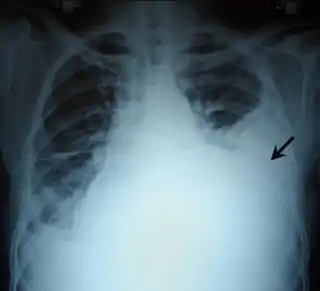

![]() Radiografía de tórax con un hemotórax izquierdo (flecha negra) | ||

Los síntomas del hemotórax son: dificultad para respirar, dolor torácico, ansiedad o inquietud, y frecuencia cardíaca acelerada. El médico puede confirmar su diagnóstico con un examen físico que puede revelar una disminución de ruidos respiratorios, la aparición de matidez a la percusión, o por medio de una radiografía de tórax.